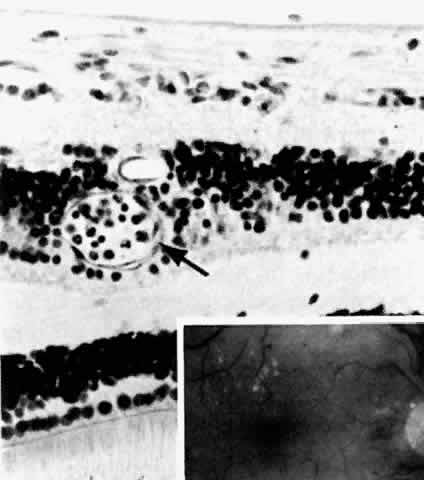

The earliest manifestation of diabetic retinopathy is the appearance of microaneurysms (Fig. 5, Color Fig. D). They appear as small red dots clinically and often are seen more readily on fluorescein angiography, where they fill and leak, with staining of the vessel wall.35 Histologically they are small “outpouchings” of the capillary vessel wall and are usually saccular but occasionally fusiform in shape. They can occur anywhere along the capillary network between the arteriole and venule.18 Some microaneurysms, however, do not fill with fluorescein and have been shown to be thin-walled capillary outpouchings filled with erythrocytes. They may represent either one stage of microaneurysm formation or a specific type of it.36

Fig. 5. Retinal capillary microaneurysm (arrow) is characterized by its thin wall and location in the capillary area of the retina (middle retinal layers) rather than the major vessel area (inner retinal layers). Inset. Fundus appearance of microaneurysms and hard or waxy exudates. (Main figure, H&E, × 176)

As shown by trypsin digestion, capillary pericytes are lost first,27 followed by endothelial cells (Figs. 6 and 7). Aldose reductase, one of the enzymes in the sorbitol metabolic pathway, is present in significant quantities in retinal capillary pericytes, but not in endothelial cells, and may thus be implicated in the formation of microaneurysms.37 The final result is an acellular segment of capillary that is nonperfused on fluorescein angiography.36